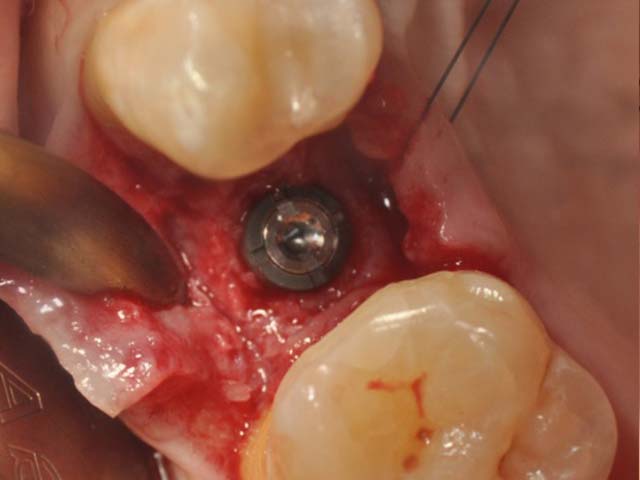

齒槽骨保存術+植牙 首頁 案例分享 人工植牙 齒槽骨保存術+植牙 STEP1拔除掉無法使用的斷裂牙根 STEP2齒槽骨保存術—使用骨粉填補拔牙傷口 術前 V.S 術後 植牙第一階段—植入牙根 植牙第二階段—製作正式假牙